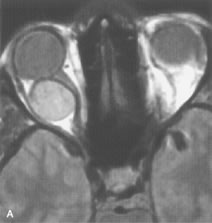

MRI is particularly helpful in the detection and characterization of subperiosteal hematomas of the orbit (Fig. 19). They are most commonly seen in the subperiosteal space of the superior orbit as well-defined masses following a traumatic injury. The signal intensity varies depending on the acute, subacute, or chronic nature of the hematoma, based on the stage of blood degradation. Fresh hemorrhages are hypointense on T1-weighted images and hyperintense on T2 images. Hematomas that are 1 to 7 days old are hypointense on both T1- and T2-weighted images. T1-weighted images of hematomas more than a week old are hyperintense due to the oxidation of deoxyhemoglobin to methemoglobin, whereas the T2 images remain hypointense.63

Fig. 19. A. T1- and (B) T2-weighted MR scans demonstrate a large acute subperiosteal hematoma (H) that lies between the cortical bone of the orbital roof and the inferiorly displaced periorthira (double arrow). The extracopal fat (arrow) and levator muscle are displaced inferiorly.